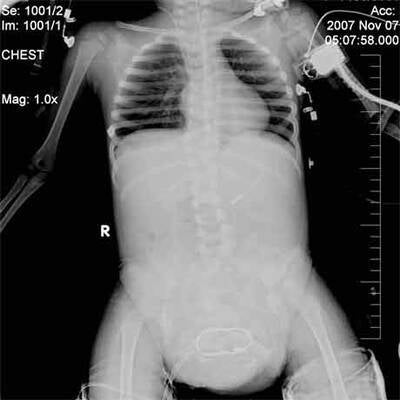

Knapp eine Woche nach einer Mammutoperation zur Entfernung von je zwei überzähligen Armen und Beinen hat sich das indische Mädchen Lakshmi am Dienstag erstmals der Öffentlichkeit gezeigt. Die Zweijährige lag im Arm ihres Vaters, hielt einen Keks in der Hand und schien gesund und aufgeweckt zu sein. Ihre Beine waren noch eingegipst. "Sie erholt sich sehr gut. Lakshmi ist jetzt nicht mehr in Gefahr", sagte Chefchirurg Sharan Patil in der südindischen Stadt Bangalore.

Sie reagiere gut auf die Behandlung und müsse daher nicht länger auf der Intensivstation bleiben, erklärte Patil. Lakshmi wurde am vergangenen Mittwoch operiert: 24 Stunden dauerte der Eingriff, 30 Ärzte waren daran beteiligt. Die Eltern des Mädchens zeigten sich danach überglücklich und erklärten, sie könnten endlich daran glauben, dass ihre Tochter ein normales Leben führen werde. Wann Lakshmi ihre Arme und Beine kontrollieren und laufen lernen kann, war aber noch unklar. Am Freitag kam das Kind wieder zu Bewusstsein. Das Mädchen habe gelächelt und die Zehen bewegt, erklärten die Ärzte. An den "neuen" Körper müsse sich Lakshmi aber offenbar noch gewöhnen.